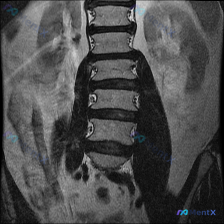

看到一张腰椎MRI冠状位片,有人说是脊柱侧弯?大家先看看影像表现

整理到一份腰椎MRI-T1序列-冠状位的影像资料,有人第一眼先提到了“脊柱侧弯”的可能性。

- 腰椎椎体序列尚可,未见明显的椎体楔形变或压缩性骨折

- 脊柱冠状位对线基本居中,未见显著的脊柱侧弯畸形

- 椎间隙高度基本维持,终板轮廓尚清晰

- 双侧腰大肌及竖脊肌群信号均匀,未见明显萎缩或脂肪浸润

- 腹膜后结构、小关节突也未见明显异常

这份资料里,影像结论和最初的关注点有点不一样。大家先看看,这种情况第一思路会怎么定?